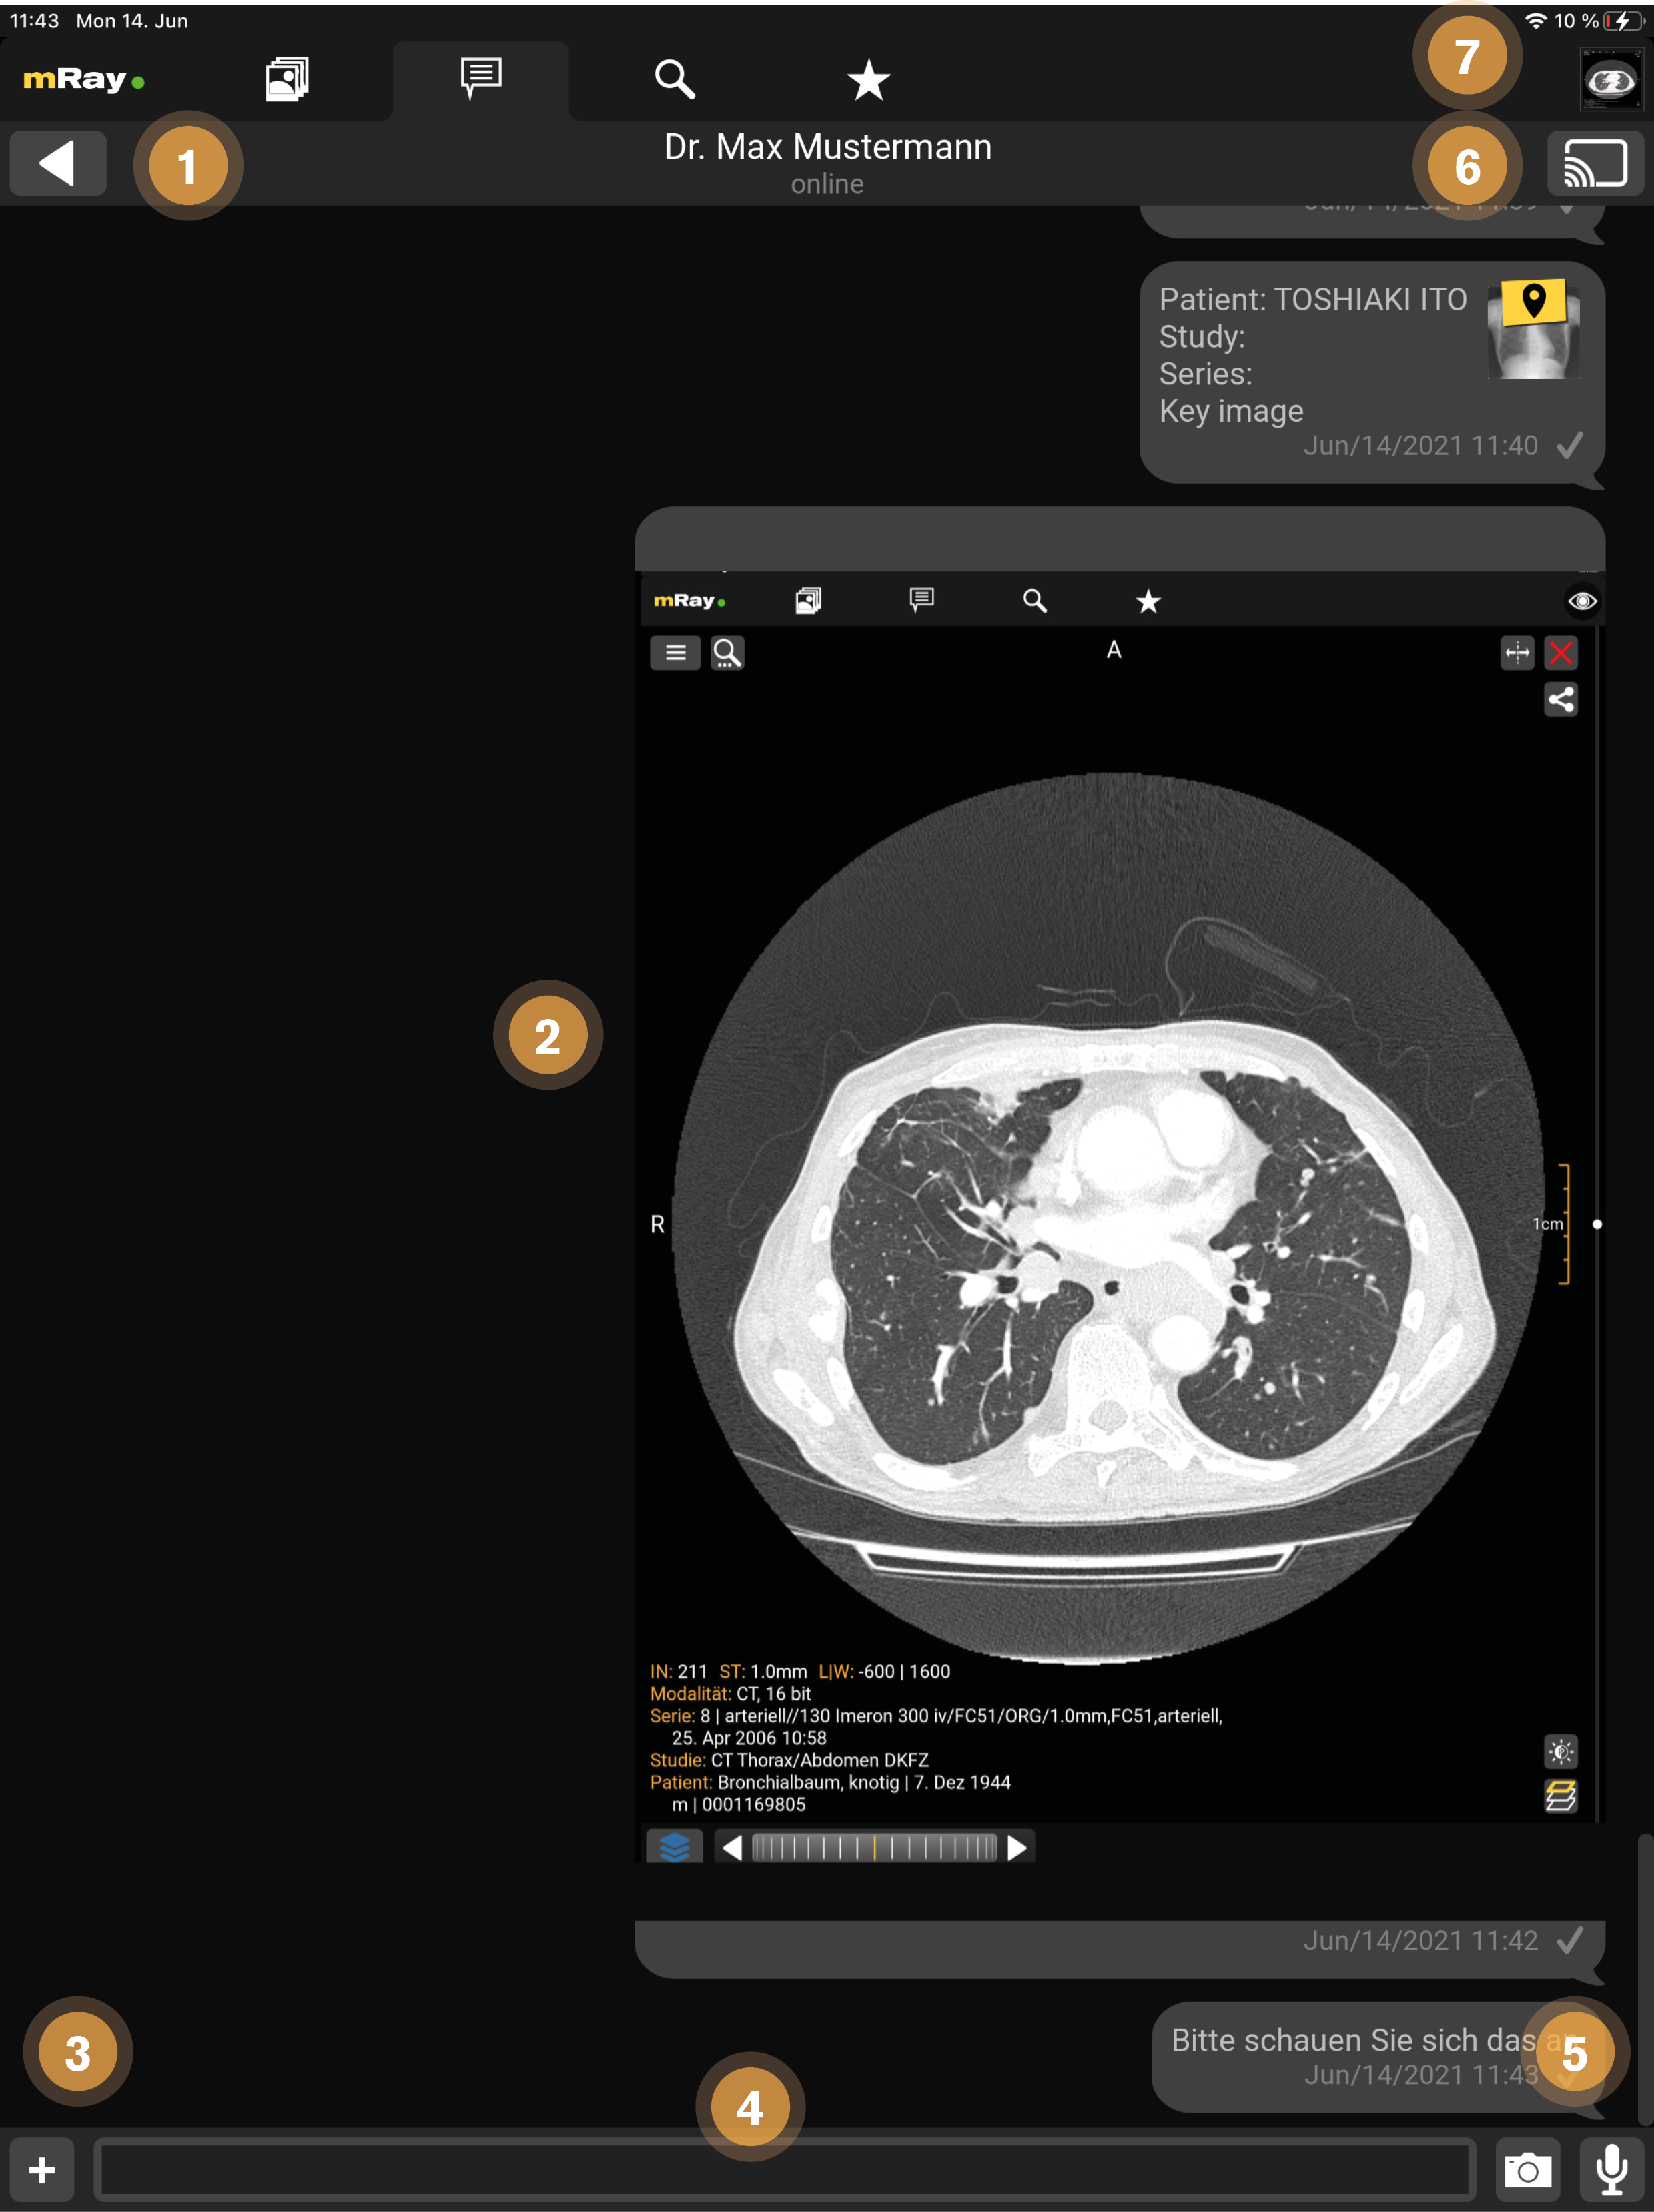

13.1. Chat

Im Chat können Nachrichten ausgetauscht werden, wie aus anderen Messaging-Anwendungen bekannt. Zusätzlich können Serien und Schlüsselbilder getauscht, und Audio Nachrichten versendet werden.

Die Ansicht stellt folgende Funktionen zur Verfügung:

-

Zurück zur Übersicht.

-

Chatverlauf: Verfügbare Serien oder Schlüsselbilder (Schlüssel-Icon über dem Vorschaubild) können durch Anklicken geöffnet werden. Bitte beachten: Wenn Sie keine Zugriffsrechte auf das Bild haben, dann wird hier eine entsprechende Fehlermeldung angezeigt.

-

Hinzufügen von Bildern aus ihrer Foto-Gallerie, welches als Fotonachricht gesendet wird (siehe Foto Nachrichten)

-

Textfeld zur Eingabe von Text-Nachrichten.

-

Mit dem "Mikrofon"-Button können Sie Audio-Nachrichten verschicken (siehe Kapitel Audio Nachrichten). Mit dem "Kamera"-Button können Sie Foto Nachrichten verschicken.

-

Mit diesem Button kann das Screensharing mit allen Beteiligten des Chat gestartet werden (siehe Screensharing).

-

Dieses Symbol zeigt an, dass im Hintergrund bereits ein Bild geöffnet ist (siehe Screensharing).